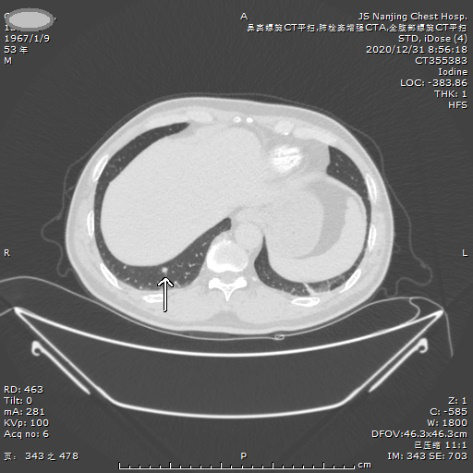

案例三 实性结节